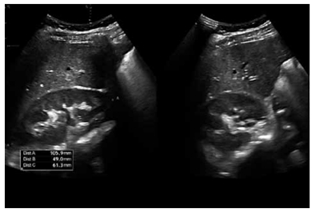

Paciente, sexo masculino, 26 anos, previamente saudável, procura pronto atendimento por edema em face e membros inferiores há 7 dias, associado à oligúria, urina “cor de Coca-Cola” e cefaleia. Relata faringoamigdalite purulenta há 3 semanas, tratada apenas com sintomáticos. Nega doenças crônicas prévias, uso de drogas ilícitas ou história familiar de nefropatias.

Exame físico: PA: 168 × 102 mmHg; FC: 88 bpm.

Edema periorbitário + edema de MMII ++/4+.

Ausculta cardíaca e pulmonar sem alterações significativas.

Exames laboratoriais:

Urina 1: proteinúria 1,8 g/24h; hematúria dismórfica; cilindros hemáticos.

Creatinina: 2,0 mg/dL (prévia desconhecida).

Ureia: 65 mg/dL.

Complemento sérico: C3 reduzido, C4 normal.

ASLO: 820 UI (elevado).

Ultrassonografia renal: rins de tamanho normal, sem alterações estruturais significativas.

Enunciado 4926045-1

(Arquivo pessoal; imagem usada com autorização)

Assinale a alternativa que apresenta corretamente o diagnóstico para o caso desse paciente.